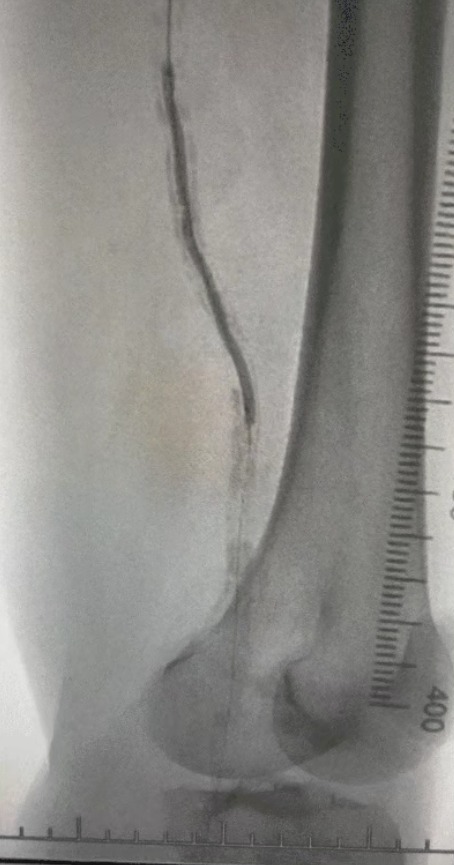

Enfoque de tratamiento

Dada la condición vascular compleja, seleccionamos el sistema de catéter de dilatación con balón periférico IVL de ThorCrack. Debido a la tolerancia limitada del paciente, se realizaron procedimientos de intervención por etapas en ambas extremidades inferiores.

Resultado quirúrgico

Después del procedimiento, la estenosis arterial mejoró significativamente, el flujo sanguíneo aumentó y la temperatura de la piel aumentó. No hubo complicaciones postoperatorias. Tanto el paciente como el equipo quirúrgico estaban muy satisfechos con los resultados.